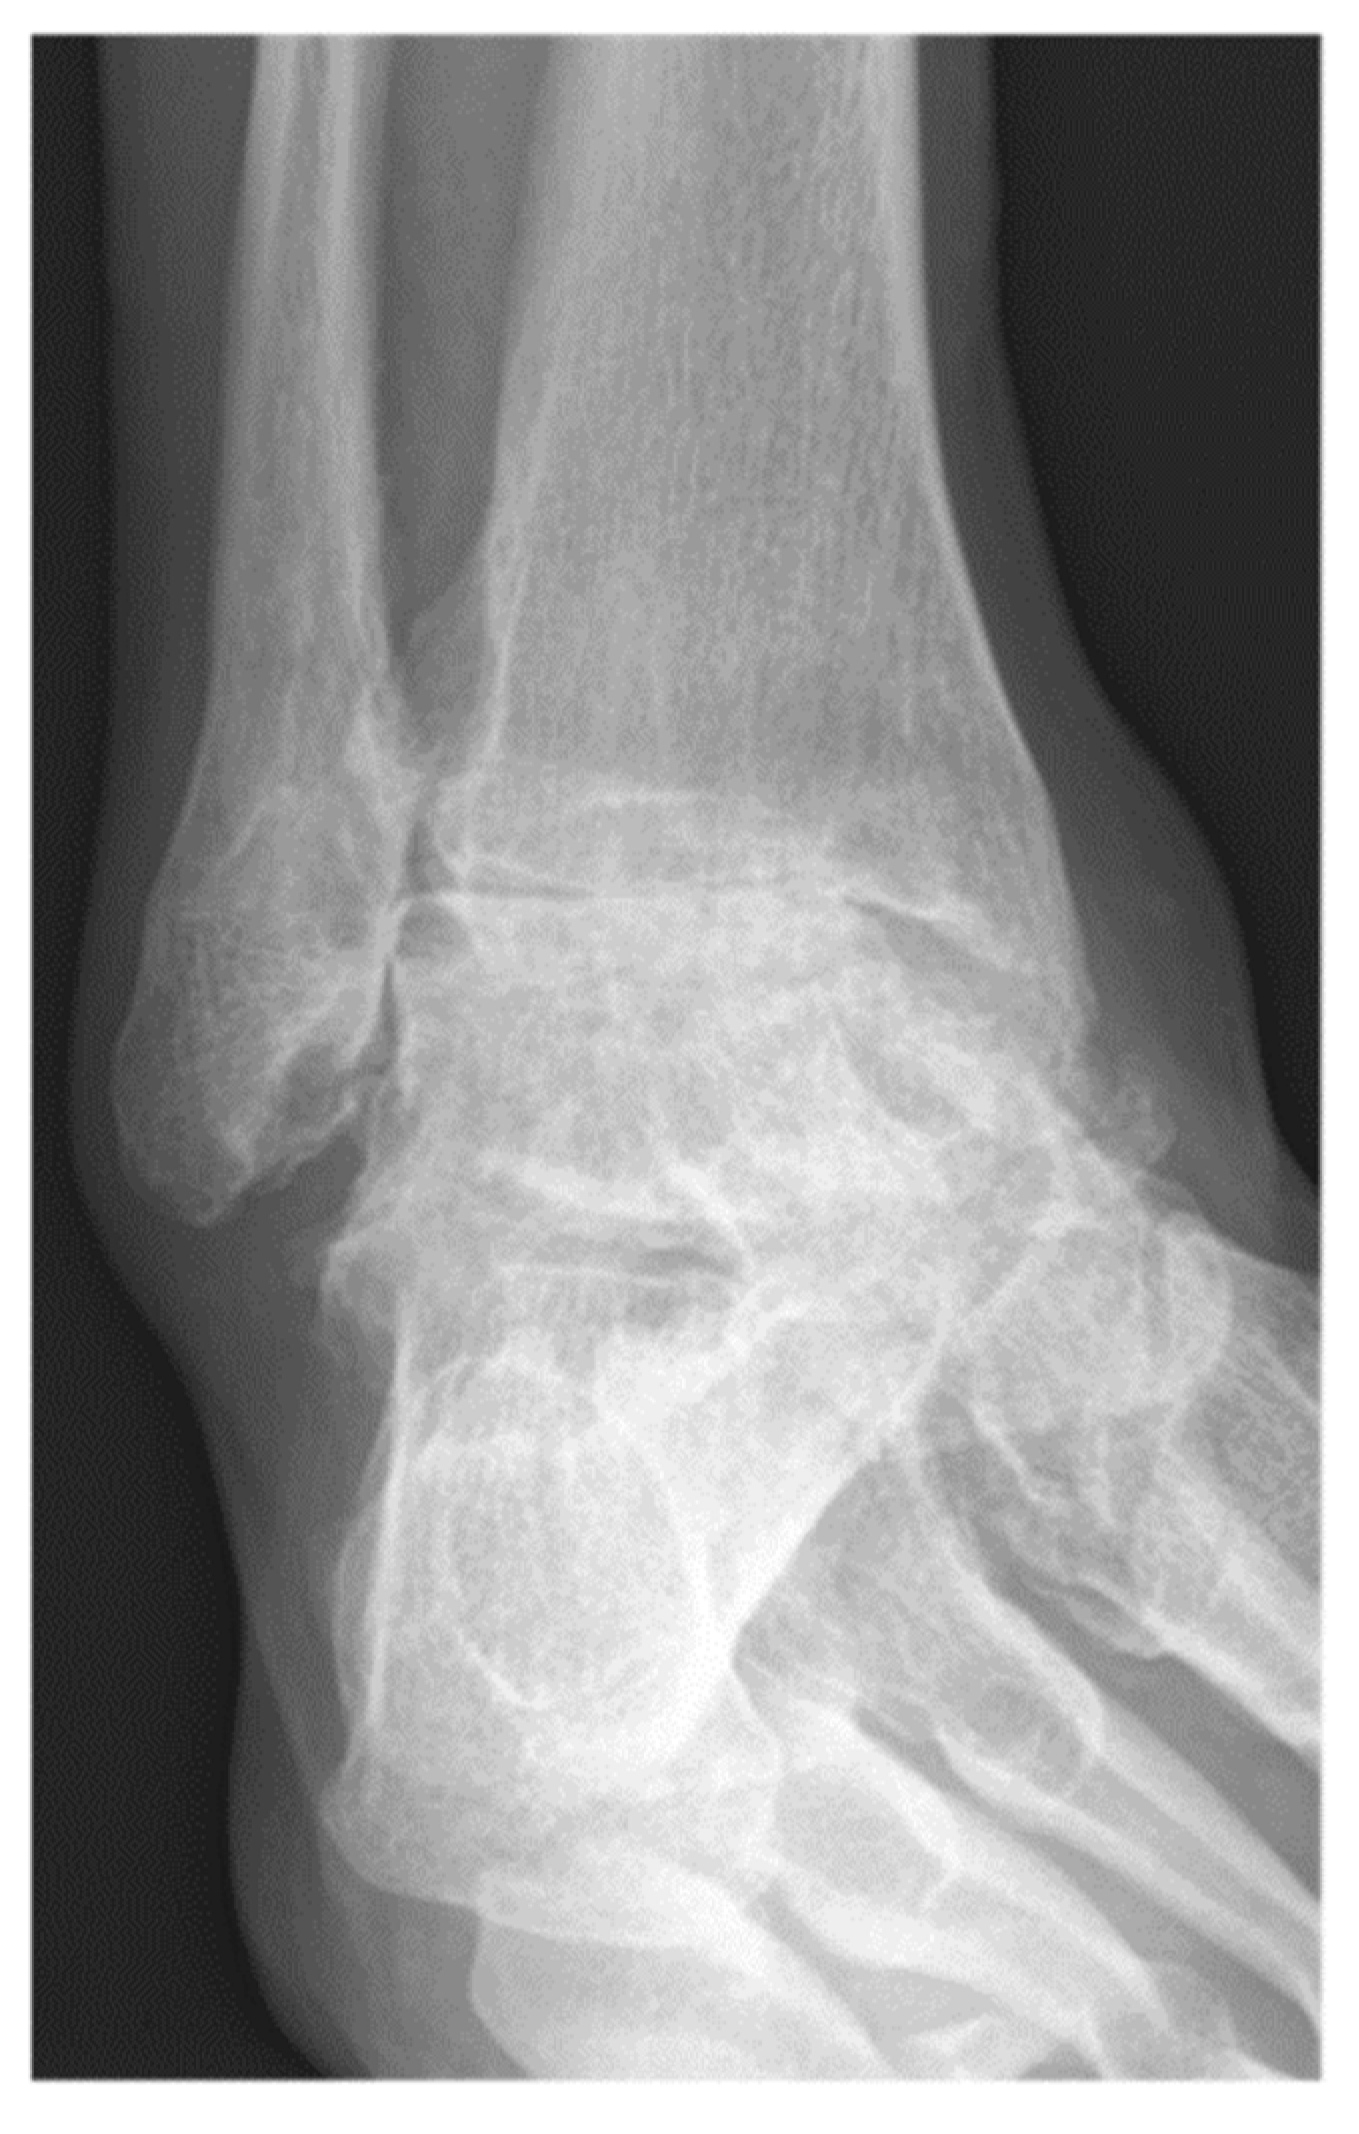

Figure 1.

A 57-year-old male patient presenting end-stage varus tibiotalar osteoarthritis.